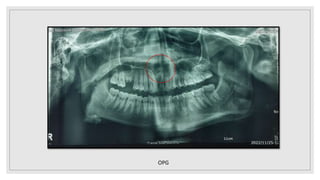

OPG

• #19 Opg revealed a ill defined, radioluceny area of size measuring 2*3cm at apex of 11,21 extending mediolaterally from distal aspect of 12 to distal aspect of 22 , superioinferiorly from floor of nasal cavity to apex of roots irt 11,21 , Internal structres is completely radiolucent with two radiopaque masses resembling the morphology of tooth suggestive of impacted supernumerary tooth. 16 – coronal loss of tooth structure and radicular portion shows widening of pdl with intact lamina dura

• #20 AOT – anterior maxilla, surrounds the crown of unerupted tooth, supernumerary tooth with displacement of adjacent toothevidences CEOC(gorlins cyst) –unilocular, pericoronal radiolucency with unerupted tooth (anterior maxillary) with displacement of adjacent tooth, evidences of calcification